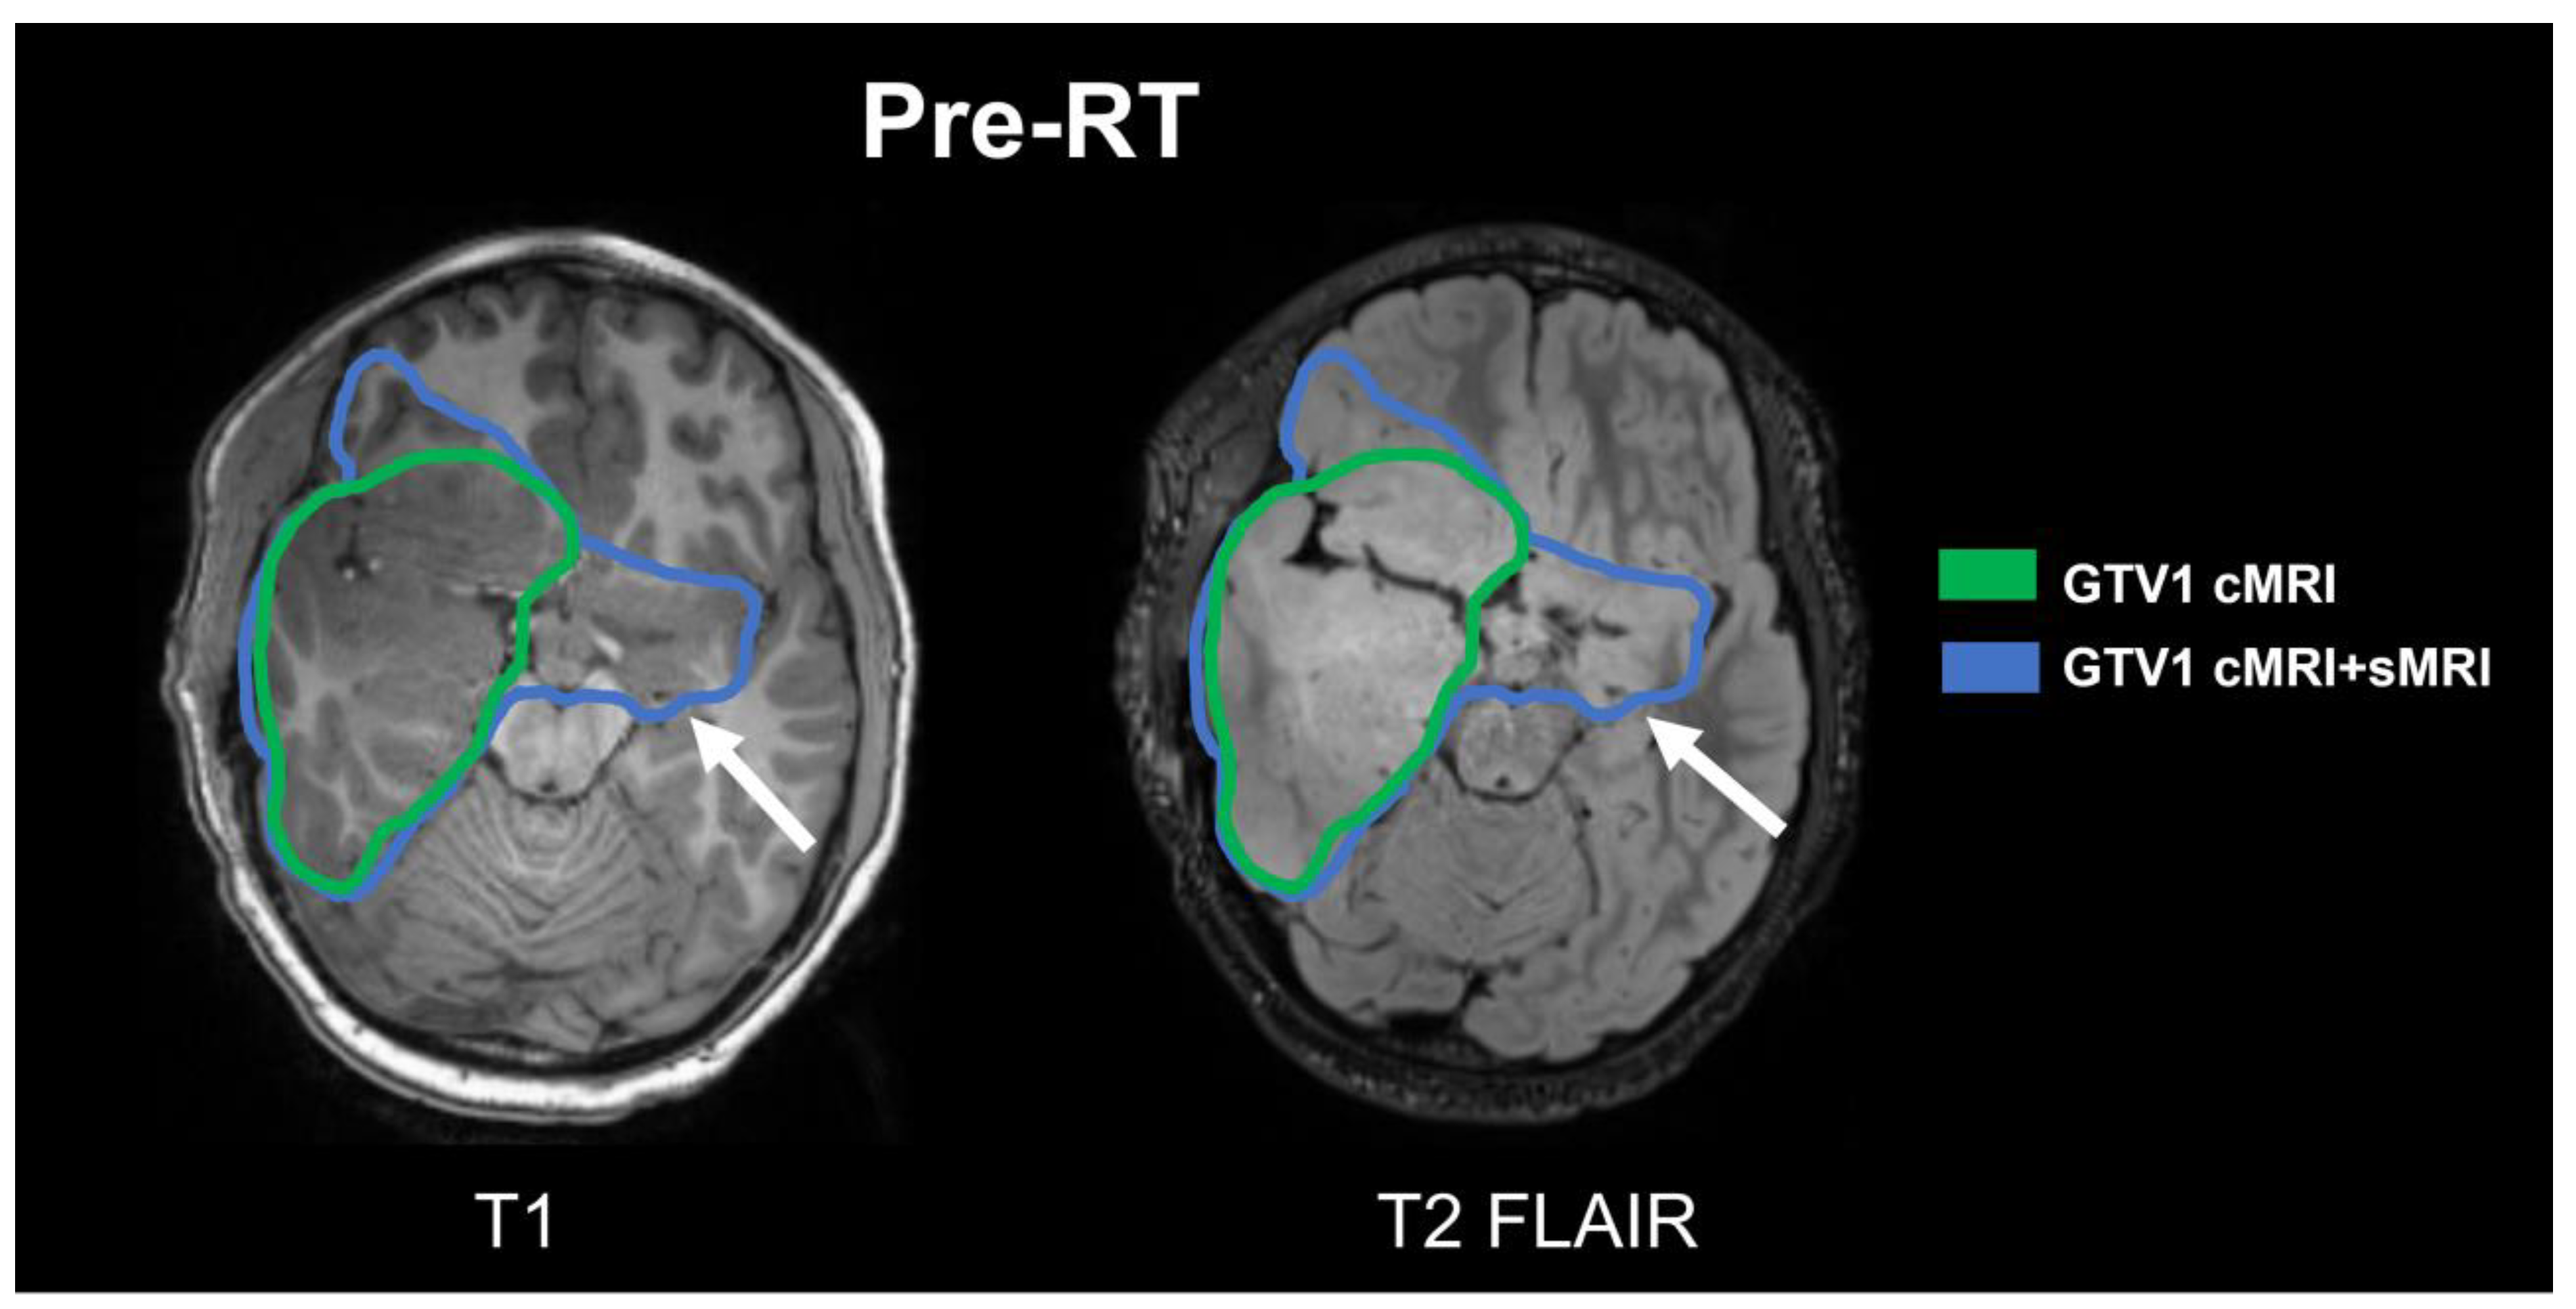

Figure 2.

Comparison of GTV1 contours. Target volumes based on cMRI alone (green) and cMRI + sMRI (blue) are shown overlaid on axial slices of the T1 (left) and T2 FLAIR (right) images. The sMRI detected an additional lesion in the left temporal lobe which is non-hyperintense on FLAIR and absent on the T1 imaging as well (white arrow). The volume of GTV1 cMRI was 207.61 cc compared to the GTV1 cMRI + sMRI volume of 297.84 cc.